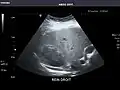

Aorta: Visualized portions normal in caliber, 16 x 15 mm.

Aorta